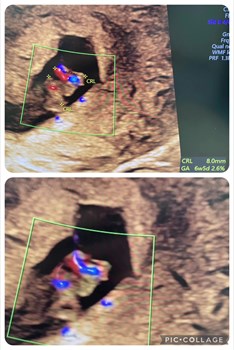

Se hele opslaget på RCN Bolig Silkeborgs Facebooksidehjertelyd_scanningsklinik En tidlig scanning kan byde på overraskelser. Her er det 2 små enæggede tvillinger, der fik sonografens opmærksomhed. 1. scanning var de bare 2.5 mm. Dette er ugen efter - u...

Se hele opslaget på Hjertelyd - scanningsklinik for gravides Facebookside